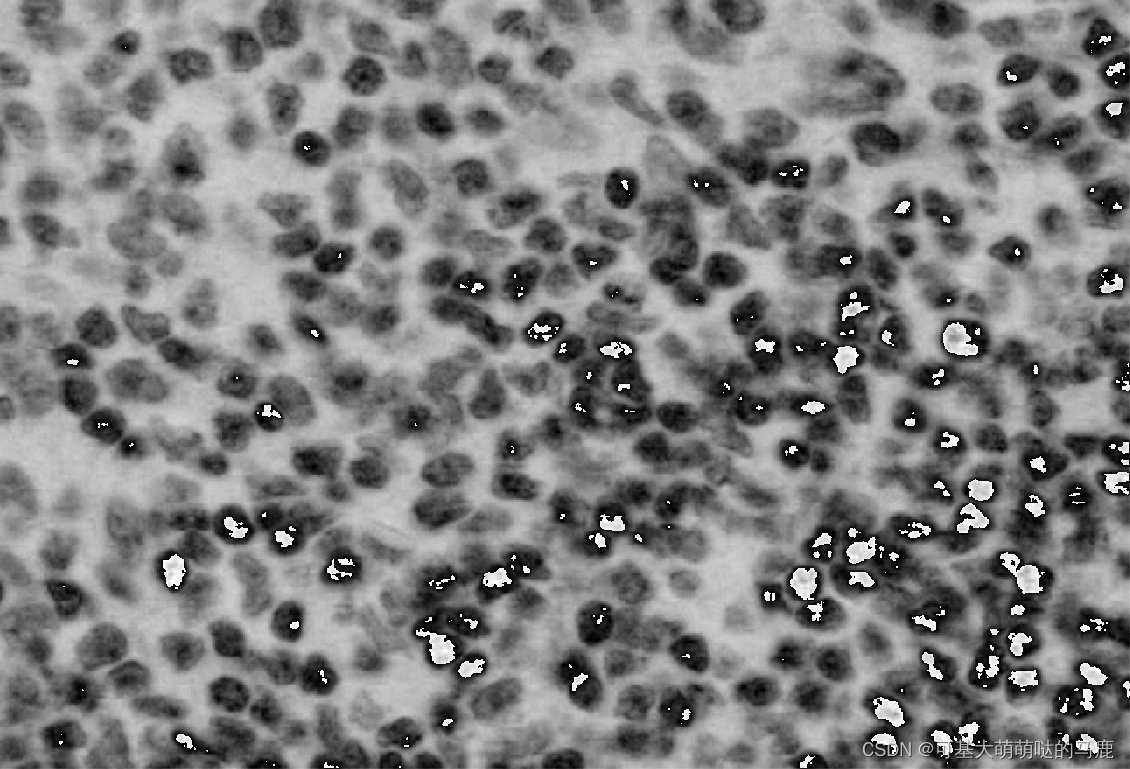

一共会有6张图的结果,最后一张是原图:

看起来是倒数第二张图结果比较好,最后在PS里面先用:图像-调整-曲线-自动,增加灰度值,再图像-调整-反相,得到我们需要的结果: